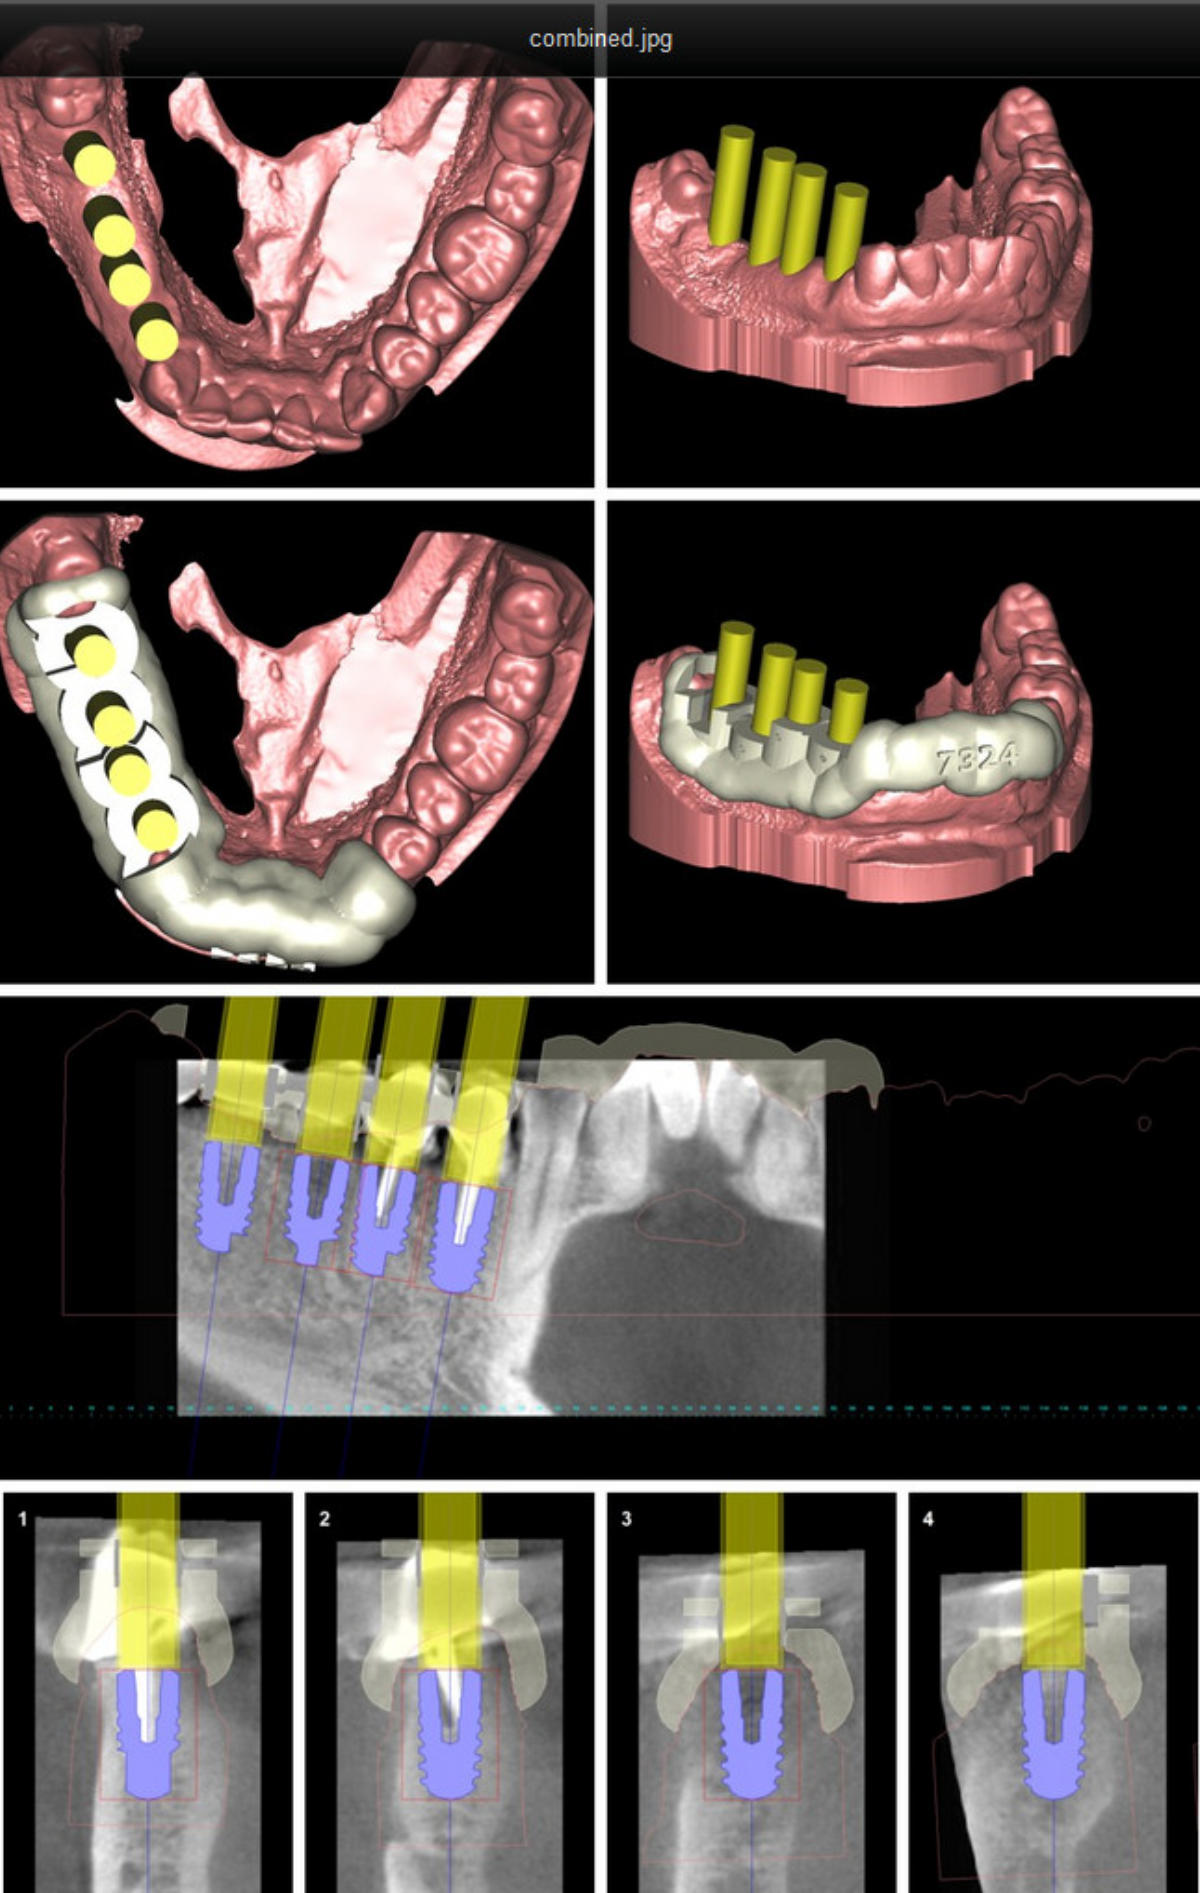

An Hand von vorliegenden dreidimensionalen Befunddaten ( 3D- Röntgenbild -DVT/ digitalisiertes Kiefermodell) wird vor dem eigentlichen Eingriff am Computer mit einer speziellen Software eine virtuelle Implantation durchgeführt ( Simulation der geplanten Operation) und auf Basis der ermittelten Daten eine Bohrschablone für das Setzen der späteren Implanate in Auftrag gegeben. Vorteile des Verfahrens sind : klinische Umsetzung und Reproduzierbarkeit der gewünschten Implantatpositionen Ermittlung des eventuell erforderlichen Bedarfs an knochenaufbauenden (augmentativen) Maßnahmen maximale Schonung benachbarter anatomischer Strukturen vor unbeabsichtigter Verletzung (Nachbarzähne, im Operationsgebiet verlaufende Nerven, Kieferhöhle etc.) Umsetzung der in der virtuellen Planung in funktioneller und ästhetischer Sicht als optimal ermittelten Implantatposition ; die individuelle intraoperative Korrekturmöglichkeit bleibt jeder- zeit gegeben Verkürzung des operativen Eingriffs durch die präoperative Operationsplanung

umfangreiche virtuelle Operationsplanung 3-D Implantatplanung Operationsschablone - angefertigt  nach virtueller Implantation umfangreiche virtuelle Operationsplanung umfangreiche virtuelle Operationsplanung

Virtuelle Implantation (Operationsplanung) am Computer